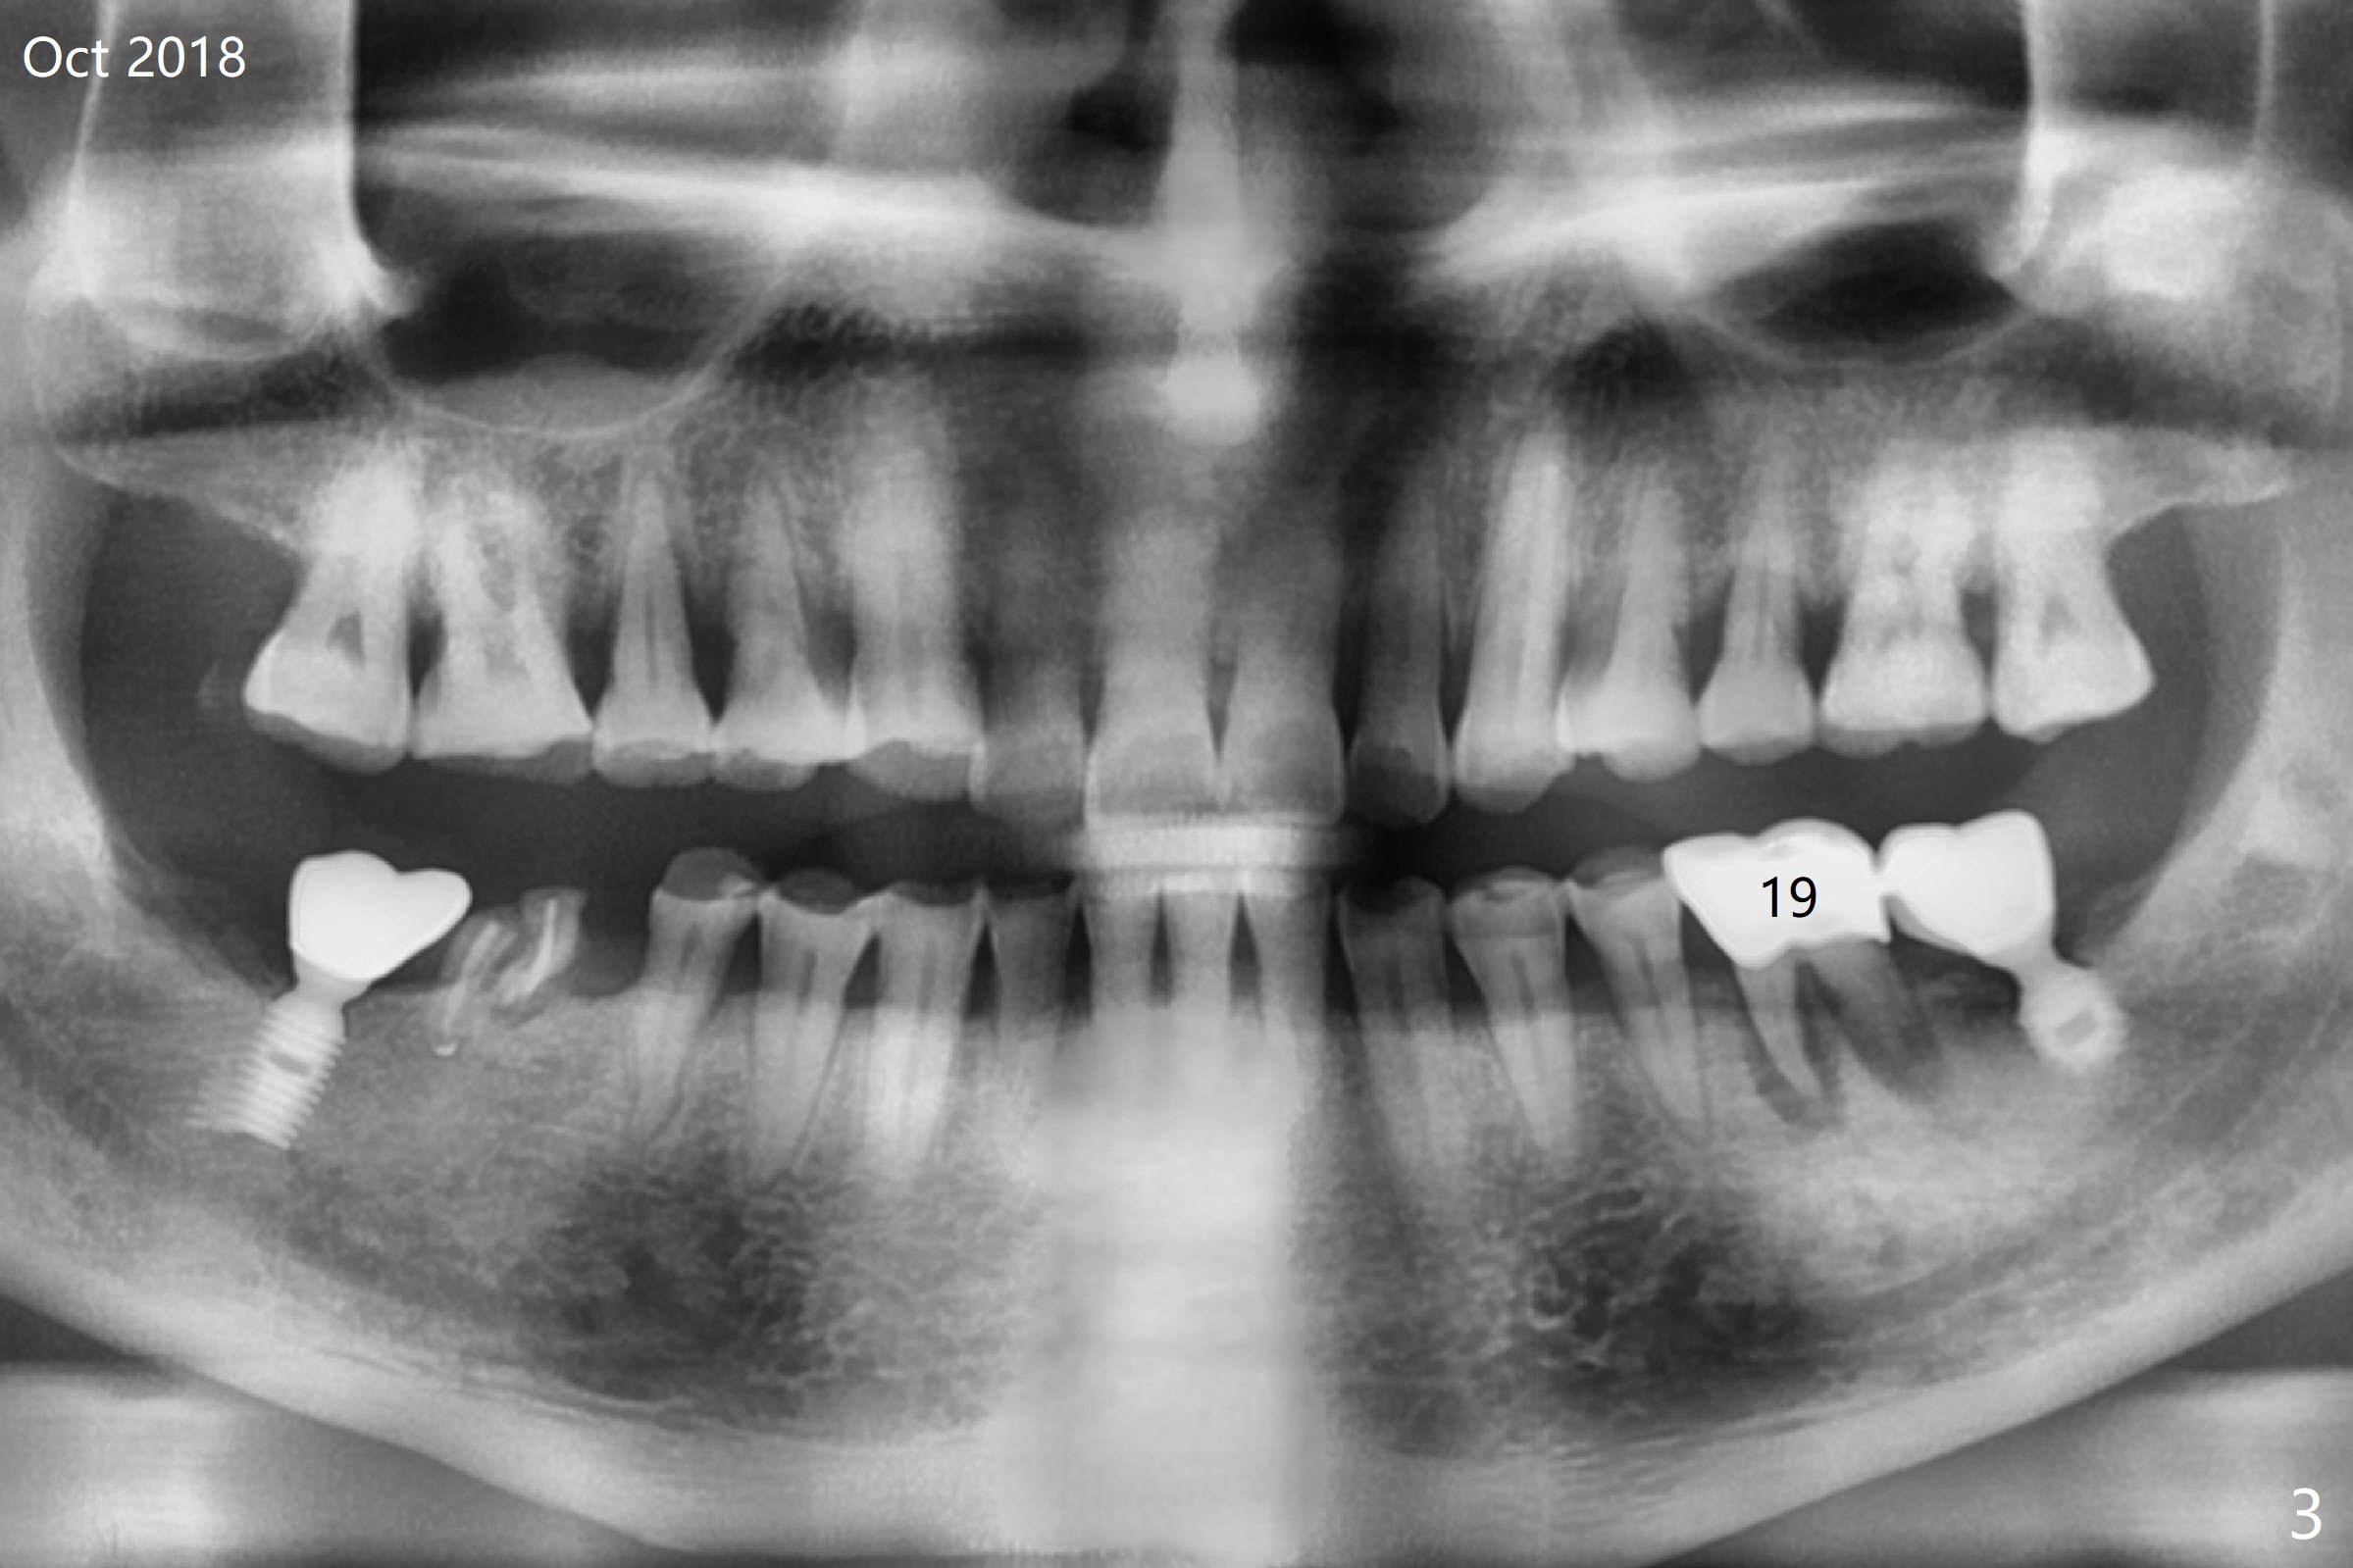

A 60-year-old man is a bruxer with severe occlusal wear (Fig.1-4). He requests implant to replace residual roots at #30 (Fig.4). A 5x11.5 mm implant will be placed. The abutment length should be limited because of limited crown height. An immediate provisional should be as low as possible.